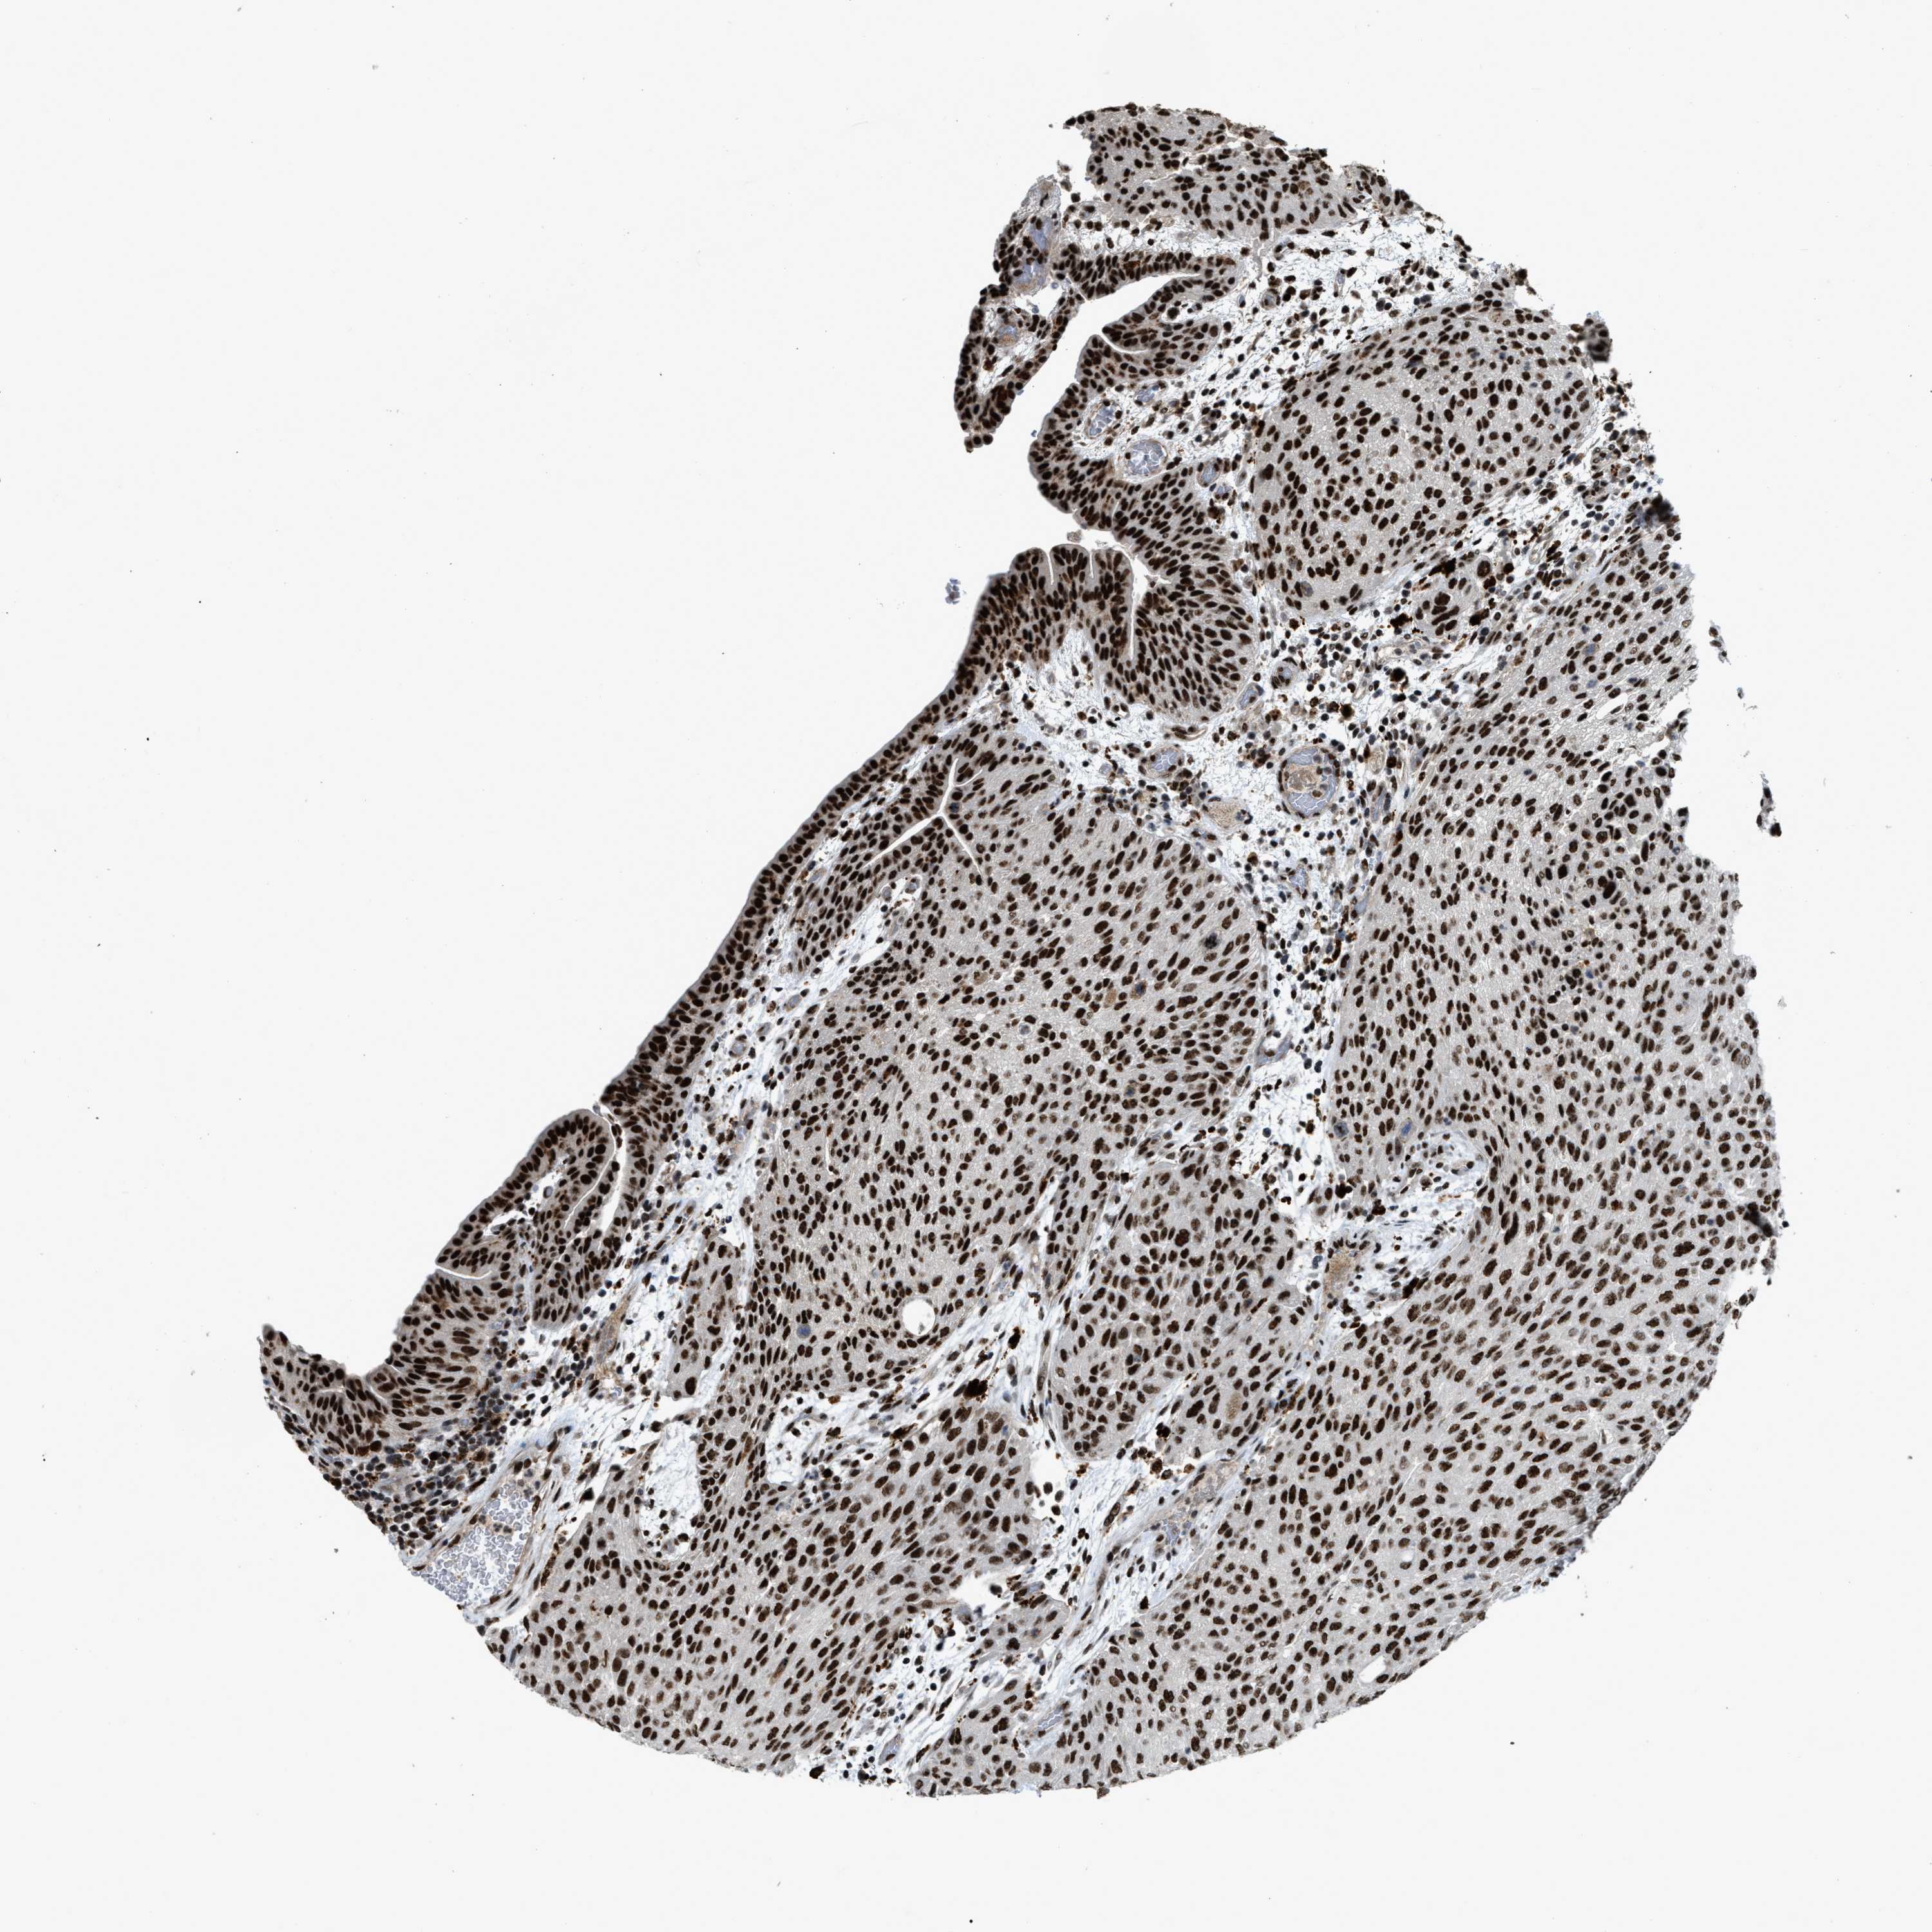

UROTHELIAL CANCER - Protein expressioni

A mouse-over function shows sample information and annotation data. Click on an image to view it in a full screen mode. Samples can be filtered based on level of antibody staining by selecting one or several of the following categories: high, medium, low and not detected. The assay and annotation is described here.

Note that samples used for immunohistochemistry by the Human Protein Atlas do not correspond to samples in the TCGA dataset.

Antibody stainingi

Antibody staining in the annotated cell types in the current human tissue is reported as not detected, low, medium, or high, based on conventional immunohistochemistry profiling in selected tissues. This score is based on the combination of the staining intensity and fraction of stained cells.

Each image is clickable and will lead to virtual microscopy that enables deeper exploration of all samples and also displays staining intensity scores, fraction scores and subcellular localization as well as patient and tissue information for each sample.

Antibody HPA019841

Antibody HPA019859

Antibody HPA029912

Staining

High

Medium

Low

Not detected

Intensity

Strong

Moderate

Weak

Negative

Quantity

>75%

75%-25%

<25%

None

Location

Nuclear

Cytoplasmic/membranous

Cytoplasmic/membranous,nuclear

Urothelial carcinoma, Low grade

Urothelial carcinoma, High grade